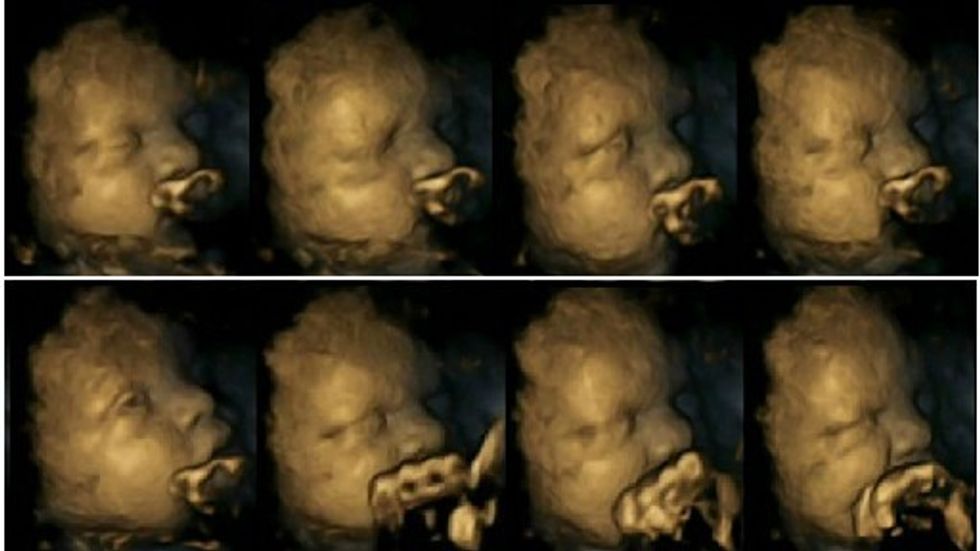

Dr Nadja Reissland ka studiuar lëvizjet me anë të një skaneri 4D ku ka regjistruar imazhet e mijëra lëvizjeve të foshnjave në barkun e nënës.

Bebet e nënave joduhanpirëse